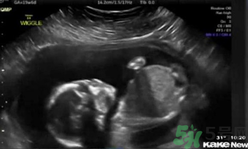

還只有5個(gè)月半的胎兒居然自己打自己的臉,這也太奇葩了,將來(lái)可能是個(gè)拳王啊。~美國(guó)堪薩斯州一個(gè)5個(gè)月半大的胎兒在母親子宮內(nèi)打自己的臉并把自己擊倒,這一幕剛好被父母用超聲波檢測(cè)儀記錄了下來(lái),并被分享到網(wǎng)上,引得眾人稱奇。這對(duì)夫婦原本還擔(dān)心兒子可能會(huì)有腦震蕩,但護(hù)士讓他們放心。凡妮莎說(shuō),這次的事件導(dǎo)致他們開始考慮兒子的個(gè)性:“我們倆都愛終極格斗。所以我們正在討論他或許會(huì)成為一個(gè)拳擊手。”